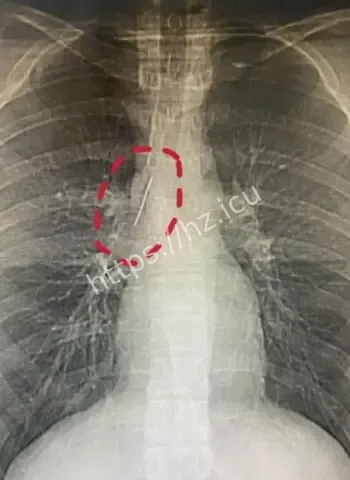

安徽17岁小伙-参军体检发现-或1岁扎入17年无恙-胸腔藏5厘米缝衣针

安徽17岁小伙胸腔藏5厘米缝衣针17年无恙

参军体检本来是查身体合不合格,谁知道成了挖宝现场。X光一扫,医生估计当时就傻眼了,这么大一根针亮闪闪地躺在胸腔里,小伙子自己都蒙圈了,心想我这身体里藏了啥秘密武器啊。幸好发现及时,要不然以后训练强度一大,万一针跑偏了,后果真不敢想。 这事儿也给大伙提了个醒,重要关口体检千万别马虎,尤其是参军这种人生大事,啥隐藏问题都能揪出来。小伙子估计现在又惊又喜,喜的是没出大事,惊的是自己居然带了17年“隐形伴侣”。

深入扒一扒,这针为啥能跟身体和平共处这么久呢。首先位置挑得好,没扎着要害器官,胸腔空间大给它留了余地。其次人体有自我保护本能,会分泌纤维组织慢慢把它包裹住,防止感染和移位。小时候扎入,身体还在发育,适应起来更容易。再次可能没带细菌进去,运气成分占大头。 这案例搁医学上都算罕见,值得研究研究,说不定以后处理类似异物就有新办法了。不过小伙子以后肯定得做个小手术取出来,不然总是个小隐患。希望手术顺顺利利,他的参军梦还能接着追,这段经历以后说出去绝对是别人听不够的传奇。